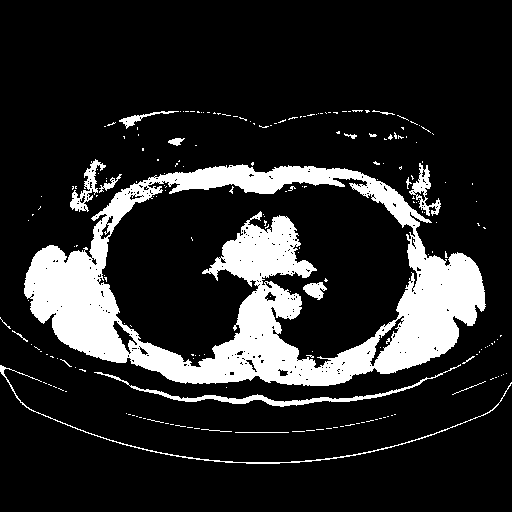

Image Grid

4Γ—3 grid: Rows show different image types (Original NATIVE, Reconstructed NATIVE, Original VENOUS, Generated VENOUS), Columns show windowing techniques (No Window, Lung Window, Mediastinum Window)

Reconstructed NATIVE CT scan (cycle consistency)

Lung window (WL -600, WW 1500 β†’ Low βˆ’1350, High +150)

Actual HU range: [-1350.0, 150.0]

Original VENOUS CT scan

Generated VENOUS CT scan (A→B translation)